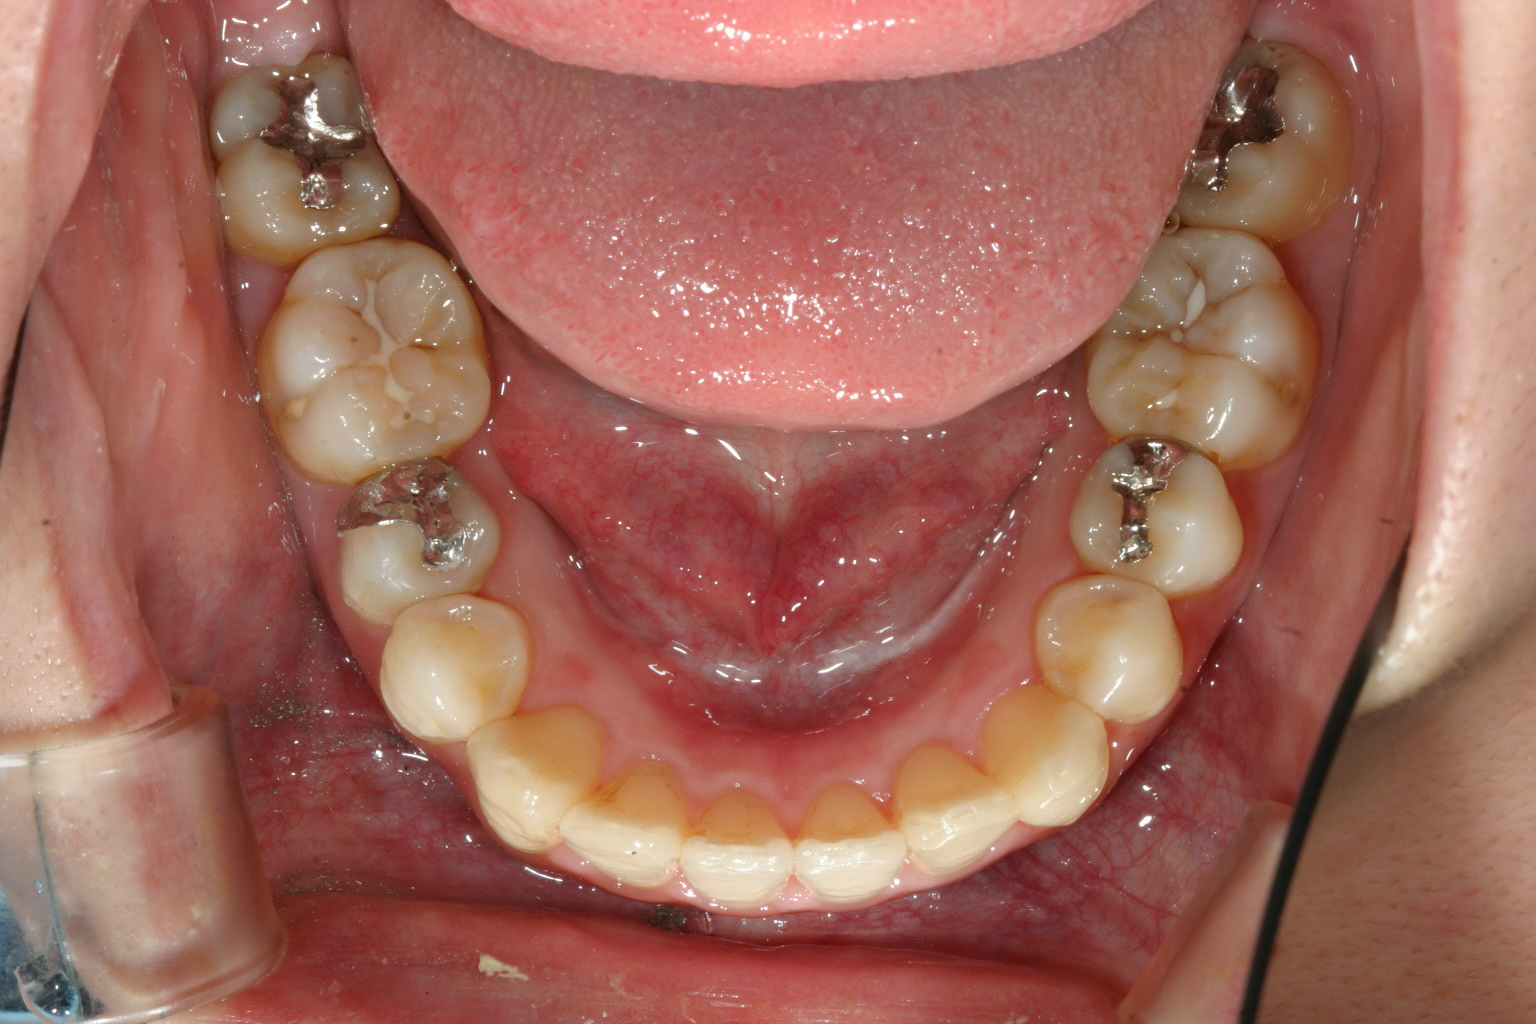

下顎も非抜歯でこの様に綺麗なアーチになりました。

抜群のオーバージェットが得られました。